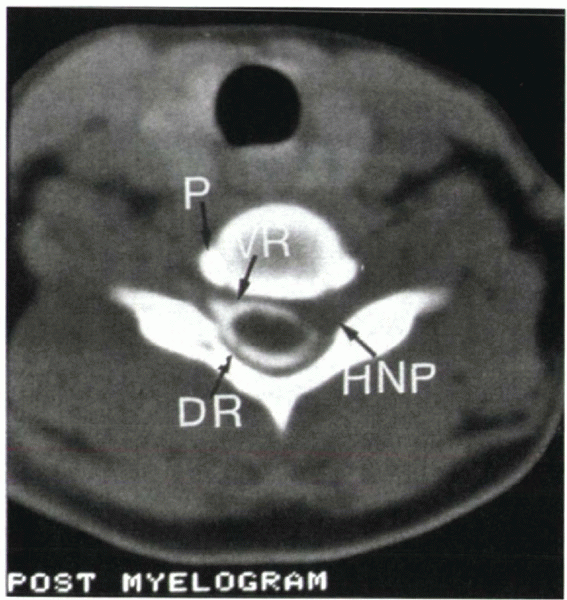

who are claustrophobic or when MRI is contraindicated or nondiagnostic.

In an acute disc herniation, CT-myelography reveals extradural filling

roots in an axial plane (Fig. 14-4).

Figure 14-4

CT-myelogram shows a herniated nucleus pulposus (HNP). Note the loss of contrast material in the left nerve root, representing compression of the exiting nerve root. DR, dorsal root; VR, ventral root; P, uncinate process of the vertebral body. |